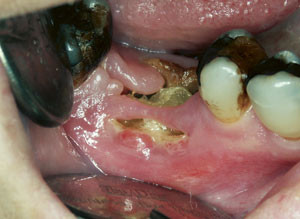

Det er velkjent at strålebehandling mot kreft i hode-hals-regionen gir orale komplikasjoner både på kort og på lang sikt (fig 1). Foreløpig er det ingen konsensus når det gjelder langtidseffekter etter cytostatikabehandling. Litteraturen på området er sparsom, men det er hevdet at salivas kvalitet og kvantitet kan være påvirket i lang tid etter endt cytostatikaterapi (9).

Spyttkjerteldysfunksjon kan gi munntørrhet, tørre og sprukne lepper, svie og brenning i slimhinnene, angulær cheilitt, proteseproblemer, smaksforstyrrelser, vanskeligheter med å tygge, svelge og snakke, karies (fig 1), progrediering av periodontal sykdom og infeksjoner, spesielt candidiasis (9). Spyttkjerteldysfunksjon kan forverre og forlenge prosessen ved mukositt og redusere munnhulens bufferkapasitet, noe som igjen øker risikoen for karies og progrediering av periodontal sykdom. Mangel på antimikrobielle proteiner som normalt skal finnes i saliva, fører også til ytterligere risiko for utvikling av karies (8).